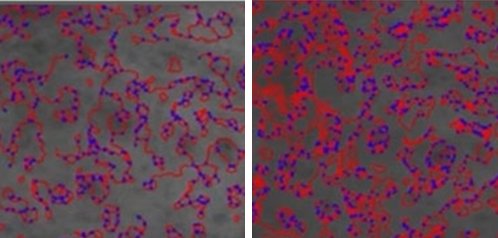

섬유아세포가 대사활동을 하는 동안 섬유아세포에 자극을 주어

콜라겐을 생성하거나, 콜라겐이 서로 합성되는 현상이 일어납니다.

섬유아세포가 대사활동을 하는 동안 섬유아세포에 자극을 주어

콜라겐을 생성하거나, 콜라겐이 서로 합성되는 현상이 일어납니다.